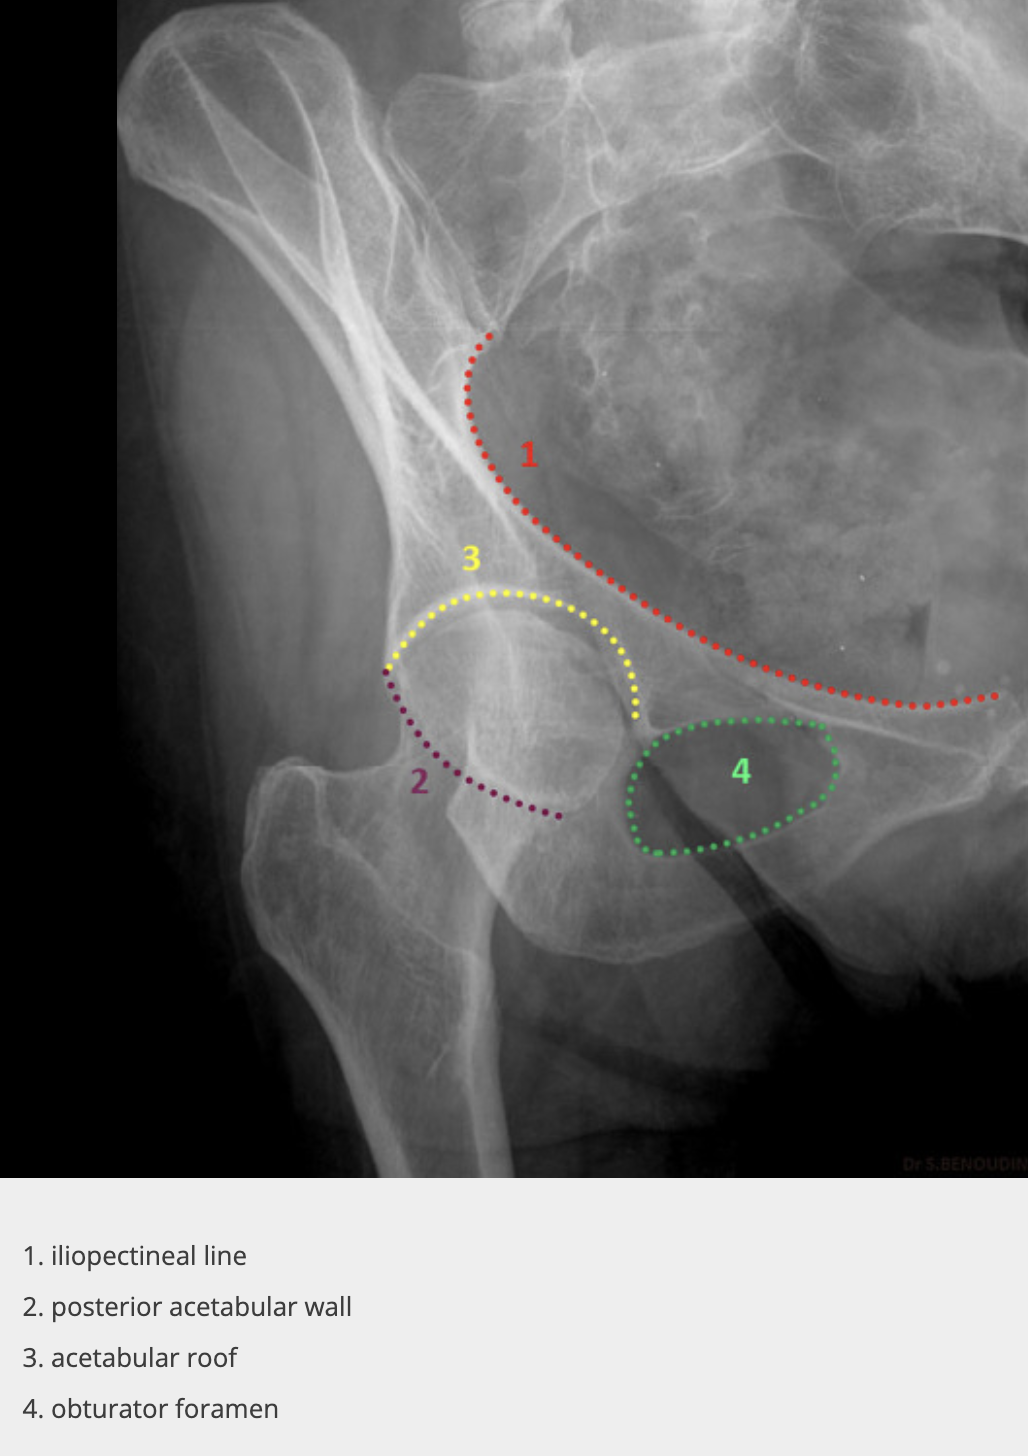

what angle for both Judet hips (typical)

45°

Judet hip - iliac view

affected/unaffected side of the pelvis is rotated 45 degrees anteriorly, allowing visualization of the 1 and 2

1 - posterior column, 2 anterior wall and rim

Judet obturator view

unaffected/affected side of the pelvis is rotated 45 degrees anteriorly, allowing visualization of the 1 and 2

affected

obturator ring, posterior wall